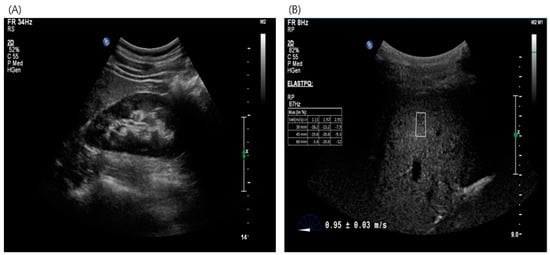

2.3. Imaging Test for Estimation of Liver Fibrosis—Acoustic Radiation Force Impulse (ARFI)